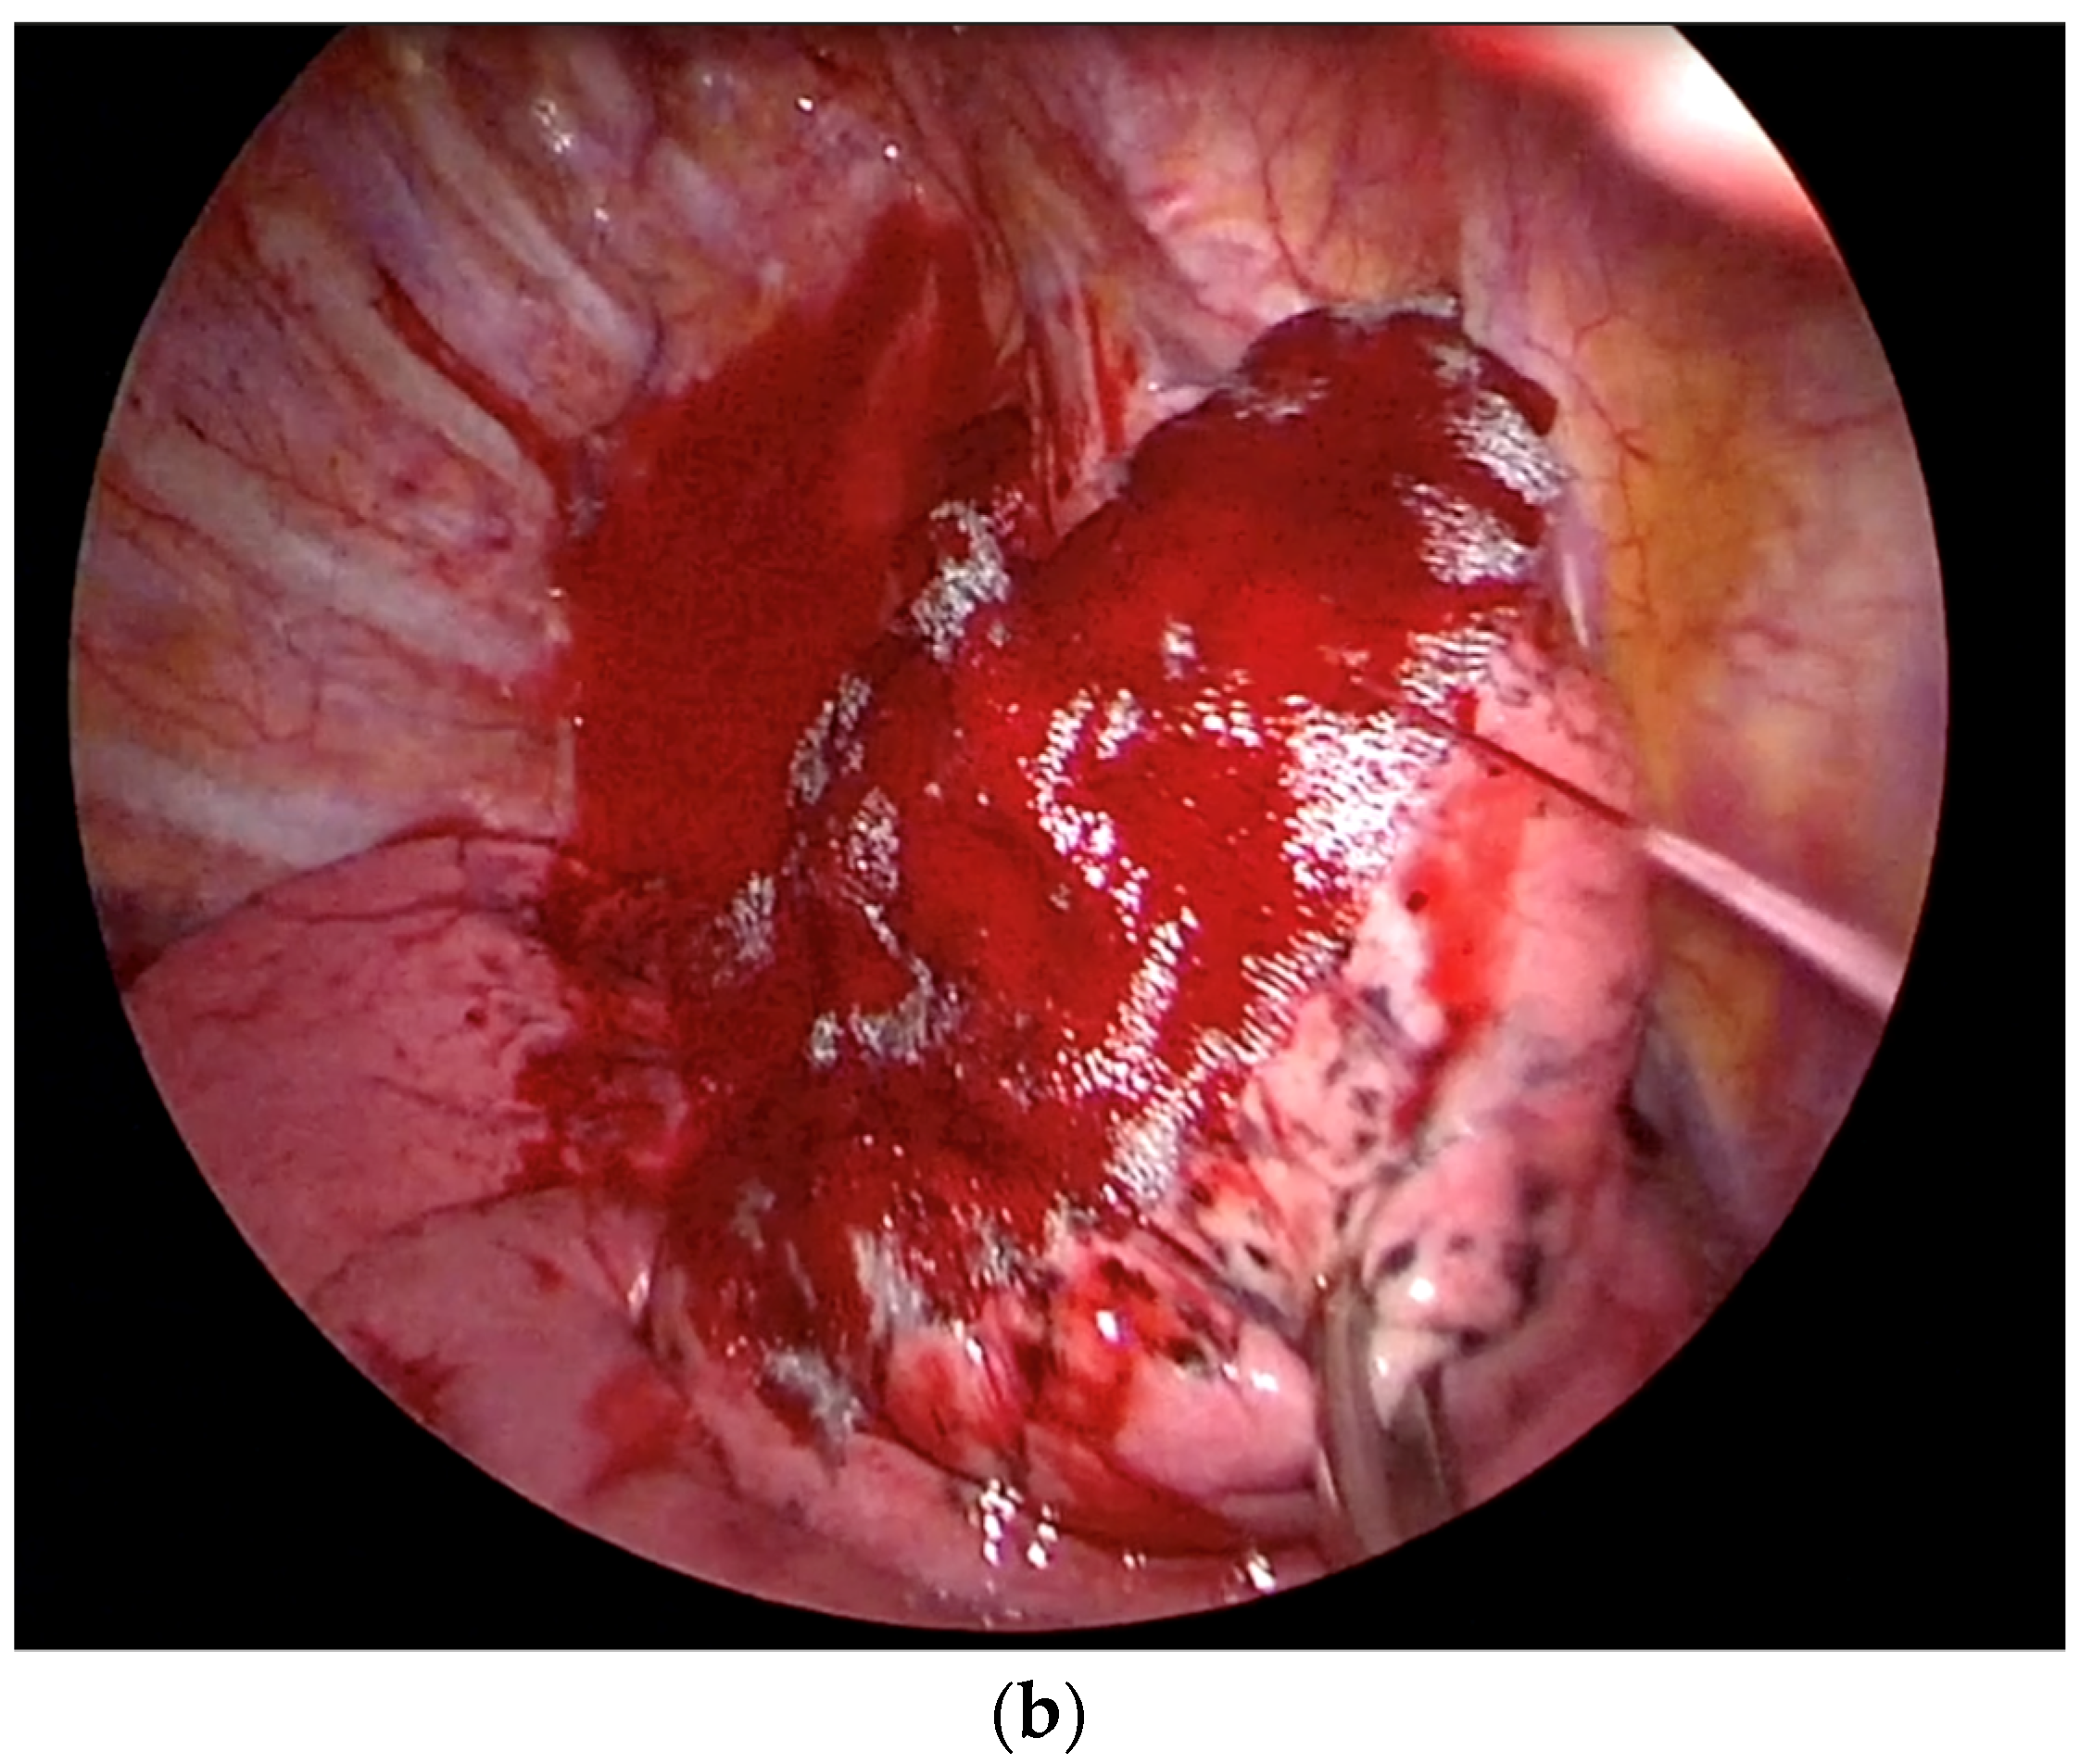

2.2. Technique for Drainless Uniportal VATS Wedge Resection